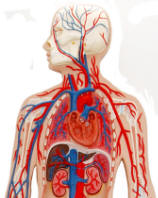

| Human Body Circulatory System -

| The muscular heart

pumps blood out through tubes or vessels, called arteries. These

branch repeatedly into microscopic capillaries that joint to form veins

that carry the blood back to heart. Our anatomical models begin

with an overview of the Circulatory System and even include functional

models. Next comes the arteries that carry the blood. The